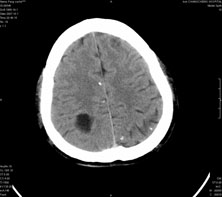

男,41岁,间断抽搐1小时,失神5分钟,bp130/90mmhg。低密度区ct值约16hu。

脑实质见多发散在的钙化点,左顶叶见一囊变灶,多考虑脑囊虫。

脑囊虫,部分囊内见头节。

脑实质见多发散在的钙化点,右颞、顶叶见囊性灶,考虑脑囊虫。

多发的囊泡(多发囊型)+多发的钙化(慢性钙化型)=混合型

顶叶最大的囊直径2.2cm,如果考虑囊虫的话,囊是不是有点儿太大了?